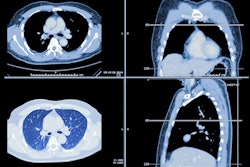

In their study, the Swiss researchers sought primarily to assess the use of radiomics to predict the malignancy of solid lung nodules. Secondarily, they wanted to compare the performance of a machine-learning algorithm with the Brock model for estimating malignancy risk on pulmonary nodules.

Using the U.S. National Lung Screening Trial (NLST) dataset, they initially gathered data for solid nodules 8 mm or larger with a primary lobar location. Of the 2,689 lung nodules in the trial, 561 were malignant and 2,128 were benign. There were 232 cases of adenocarcinoma and 115 cases of squamous cell carcinoma.

Next, the researchers used 3D Slicer software to perform semiautomatic segmentation on a subset of 614 lung nodules, including 315 malignant nodules and 299 benign lesions that were chosen randomly. The malignant cases included 221 adenocarcinomas and 94 squamous cell carcinomas. Using the open-source Pyradiomics software, they then extracted more than 120,000 radiomics features from the CT images, as well as the patient's demographic and clinical data, said presenter Dr. Steve Martin.

Of the nodules included in the study, 80% were used for training the machine-learning algorithm, while 20% were set aside for testing. The machine-learning algorithm, which used principal component analysis (PCA) and a support vector machine (SVM) classifier, considers both the radiomics features and the patient's demographic and clinical data in characterizing the lung nodules, according to the researchers.